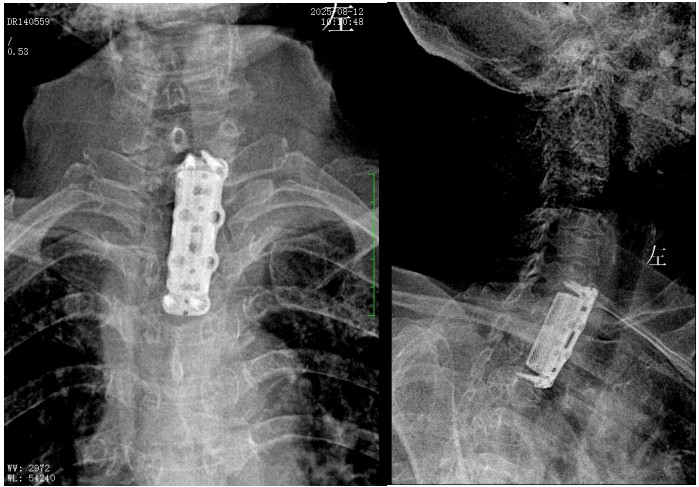

錢軍博士組織團(tuán)隊(duì)進(jìn)行了詳盡的術(shù)前討論,充分的術(shù)前準(zhǔn)備后,于8月10日為患者實(shí)施了“前路病灶清除、人工椎體植入、植骨融合內(nèi)固定術(shù)”。順利完成了徹底清除病灶,椎管減壓解除脊髓壓迫,矯正后凸畸形,重建脊柱穩(wěn)定性的手術(shù)目標(biāo)。